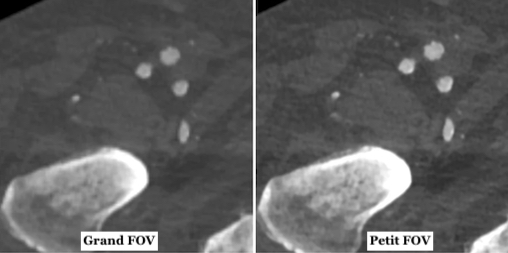

Il s’agit plus globalement d’évaluer l'impact du champ de vision reconstruit (FOV) sur la qualité de l'image en angiographie par tomodensitométrie (CTA) des membres inférieurs. Pour cette étude, un total de 100 examens CTA des membres inférieurs ont été acquis sur un scanner multidétecteur 2 × 192 coupes. Trois ensembles de données différents ont été reconstruits couvrant les deux jambes (taille FOV standard) ainsi que chaque jambe séparément (taille du

FOV réduite). La qualité subjective de l'image a été évaluée pour les différents segments de vaisseaux (fémoral, poplité, crural, pédieux) par trois lecteurs à l'aide d'une échelle de Likert semi-quantitative. De plus, la qualité d'image objective a été évaluée à l'aide d'une métrique de qualité d'image automatisée pour chaque coupe.

Une reconstruction séparée des deux membres inférieurs aboutit à une meilleure qualité des images

L'évaluation subjective de la qualité de l'image a montré une concordance presque parfaite entre les évaluateurs. La qualité d'image obtenues à partie des petits FOV a été notée significativement plus élevée par rapport aux grands FOV, pour tous les patients et segments de vaisseaux, avec une différence plus nette pour les petits vaisseaux. La différence des scores moyens entre le groupe grand FOV vs petit FOV était de 0,68 pour le niveau fémoral, 0,83 pour le niveau poplité, 1,12 pour le niveau crural et 1,08 pour le niveau pédieux. La métrique objective de la qualité de l'image a également démontré une amélioration significative de celle-ci dans les ensembles de données relatives aux petits FOV.

Les chercheurs en donc conclu que la reconstruction latérale séparée de chaque jambe dans le CTA des membres inférieurs à l'aide d'un petit FOV de reconstruction améliore considérablement la qualité de l'image par rapport à une reconstruction standard avec un grand FOV couvrant les deux jambes.